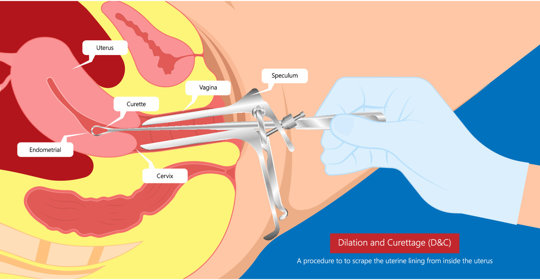

產後隱憂揭秘:白色惡露症狀、形成原因與預防